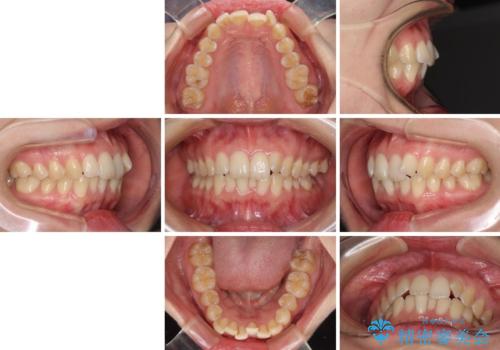

- 上下前歯のデコボコと深い咬み合わせを気にして来院された患者様です。

インビザラインによる上下歯列の拡大と、IPR(歯と歯の間を削る)にるスペースの獲得により、前歯のデコボコを改善することとしました。

上の前歯をもう少し整えたかったのですが、患者様の治療を早く終了させたいという希望により、細かい叢生を残しての終了となりました。